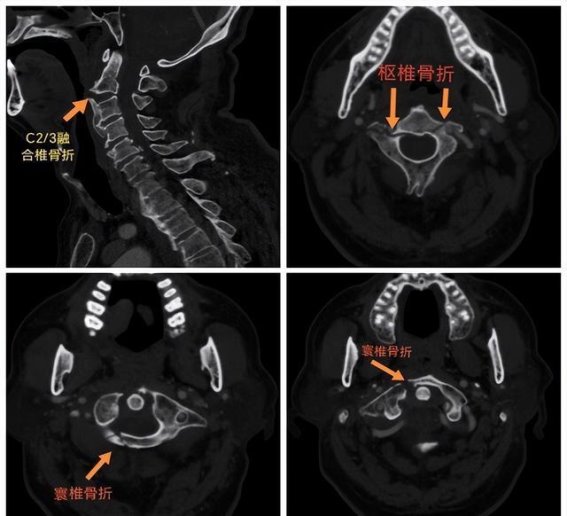

这三位患者的病情可谓复杂至极。第一名患者,罹患了DISH病(即脊柱后纵韧带钙化症),其寰椎和枢椎均发生骨折,并且C2/3椎体也有融合性骨折。第二名患者则患有强直性脊柱炎,造成了齿状突的骨折,伴随C6/7椎体的融合性骨折。第三名患者更为特殊,其脊柱骨骺发育不良,且合并齿状突的陈旧性骨折。三个病例中,患者均在外伤后出现了明显的颈部疼痛、活动障碍,并伴有不同程度的神经症状。

患者在经历了严重的外伤后,急需接受针对性治疗。赵伟教授对这三位患者进行了详细的体格检查和影像学评估,发现他们的脊柱问题远不止寰枢椎骨折那么简单。基于此,赵教授和团队成员迅速组织了麻醉科、手术室等多学科专家会诊,并结合患者的特殊病情和个体化需求,制定了精确的手术方案。特别是对于DISH病患者和强直性脊柱炎患者,由于脊柱的严重融合,脊柱的稳定性已经发生了极大的改变,手术难度之高,几乎没有前例可借鉴。

针对第一位DISH病患者,赵教授团队决定采用寰枢椎有限固定技术,以保留寰枢椎的活动度,同时恢复寰枢椎及C2/3的稳定性。此举旨在避免过度固定带来的活动受限,同时保证骨折部位的良好恢复。对于第二位强直性脊柱炎患者,赵教授团队选择了枕颈融合椎弓根螺钉固定术和颈前路多节段椎体固定术相结合的手术方案。此举有效地解决了患者的齿状突骨折问题,并稳定了其脊柱。而第三位脊柱骨骺发育不良患者,手术方案选择了枢椎椎板螺钉和寰椎侧块螺钉固定技术,以重建寰枢椎的稳定性,避免了由于骨骼发育不良可能带来的并发症。